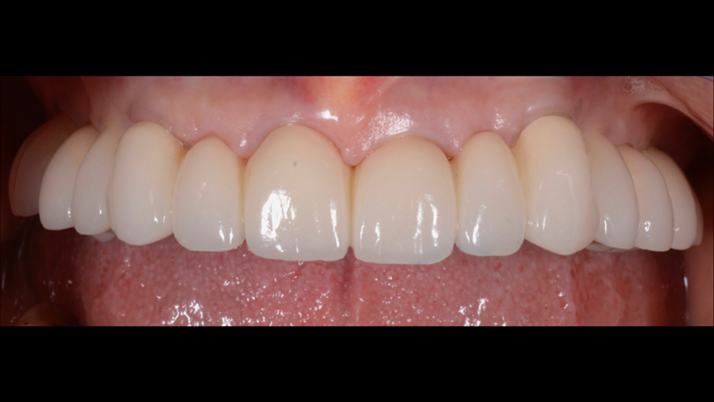

Clinical case: AFull transition from natural teeth to all-on-6 bridges

with AnyRidge implants

- Courtesy of Dr. Rabih Abi Nader, UAE -

Keywords

Full-mouth rehabilitation, minimal layering, Zirconia, all-on-6, life changing result, edentulous ,Dr. Rabih Abi Nader, AnyRidge

Products:

AnyRidge implant system

“AnyRidge shows excellent esthetic results

with Zirconia prosthesis in full-mouth rehabilitation case . ”